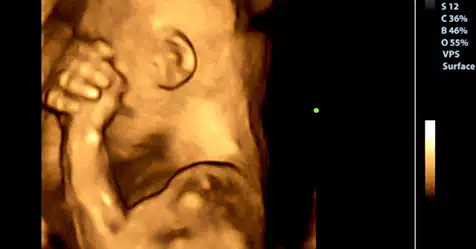

Esta pesquisa descobriu que quando um bebê está no útero de sua mãe, é um participante ativo no seu próprio desenvolvimento, especialmente porque ele está a recolher informação para a vida extra uterina durante esse período. Um dos achados mais impressionantes do trabalho científico de que também participaram Elysia P. Davis e Laura M. Glynn é que o bebê pode sentir o estado psicológico da mãe.

À medida que o bebê cresce, recebe constantemente mensagens de sua mãe e estas não são apenas circunscritas para ouvir seu batimento cardíaco ou ouvir a música que sua mãe o coloca perto de sua barriga: vai além. Nesse estágio, o bebê recebe sinais químicos através da placenta, que incluem o estado mental de sua mãe. Os hormônios que as mães produzem quando experimentam emoções passam pela placenta.

Assim, se a mãe está gravemente triste ou deprimida, o bebê sente isso. Esse estado emocional afeta seu desenvolvimento durante boa parte de sua vida. A longo prazo, ter uma mãe deprimida poderia levar a problemas neurológicos e transtornos psiquiátricos , diz Sandman.